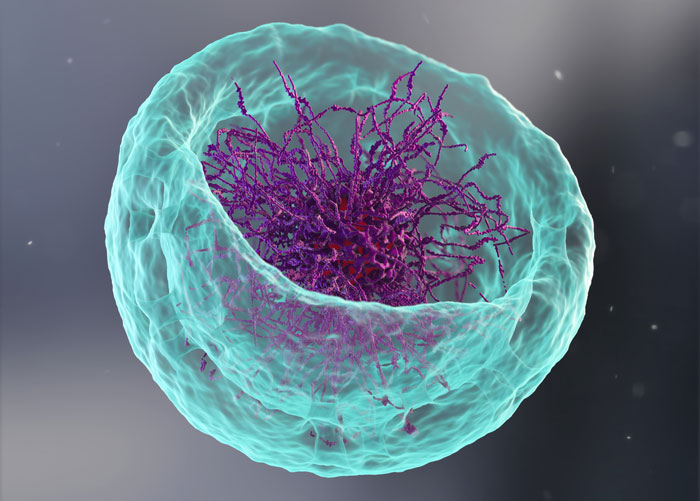

B cell discovery could supercharge future vaccine development

New research reveals how B cells balance mutation and clonal expansion to refine their antibodies. This discovery could lead to more targeted and effective vaccine designs for various diseases.